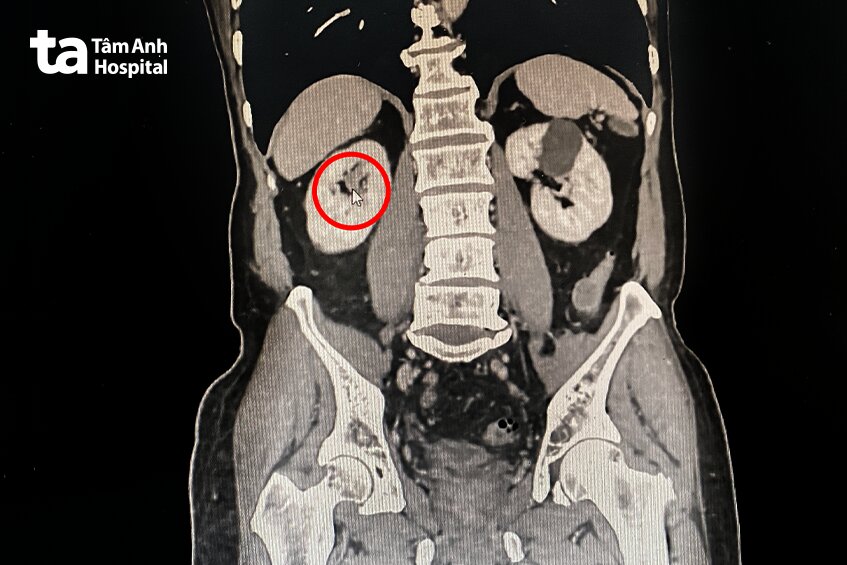

PGS.TS.BS Vũ Lê Chuyên, Giám đốc Trung tâm Tiết niệu – Thận học – Nam khoa, Bệnh viện Đa khoa Tâm Anh TP.HCM cho biết, kết quả chẩn đoán hình ảnh chụp CT 1975 lát cắt tại Bệnh viện Đa khoa Tâm Anh TP.HCM ghi nhận ông Khang có một khối u nằm kín đáo ở đài trên thận phải. Để xác định u lành hay ác tính, bác sĩ nội soi bàng quang, niệu quản và thận bằng ống soi mềm, nhằm tiếp cận khối u để lấy mẫu sinh thiết. Kết quả giải phẫu bệnh cho thấy người bệnh bị ung thư niệu mạc (ung thư biểu mô đường tiết niệu trên), khối u này đặc biệt có thể gây ảnh hưởng đến hệ tiết niệu.